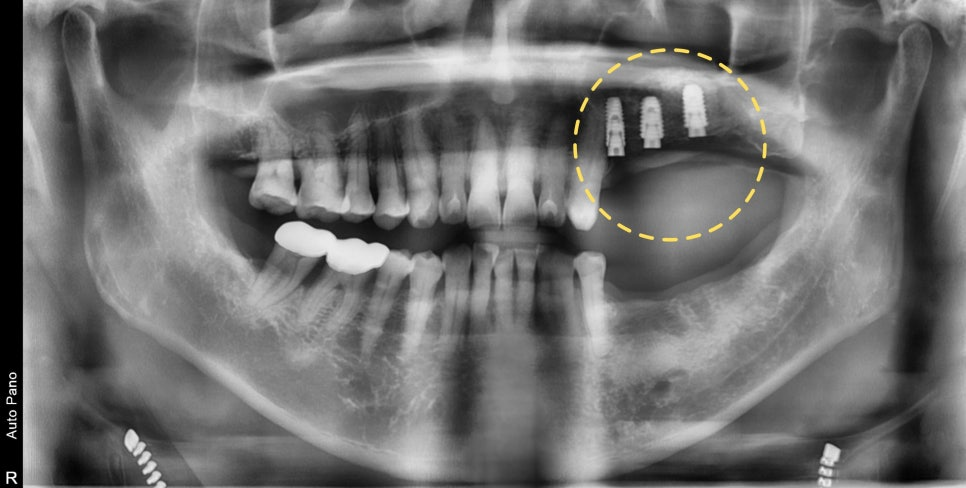

23.08.25 — 상악동 거상술 전 / 23.11.10 — 시술 후

발치 후 6개월 뒤 내원 시 안쪽 뼈 상태가 좋지 않아 뼈이식과 상악동 거상술이 모두 필요한 상황이었습니다. CT 화면을 직접 보여드리며 근거를 설명드린 뒤, 위쪽을 먼저 진행했습니다.